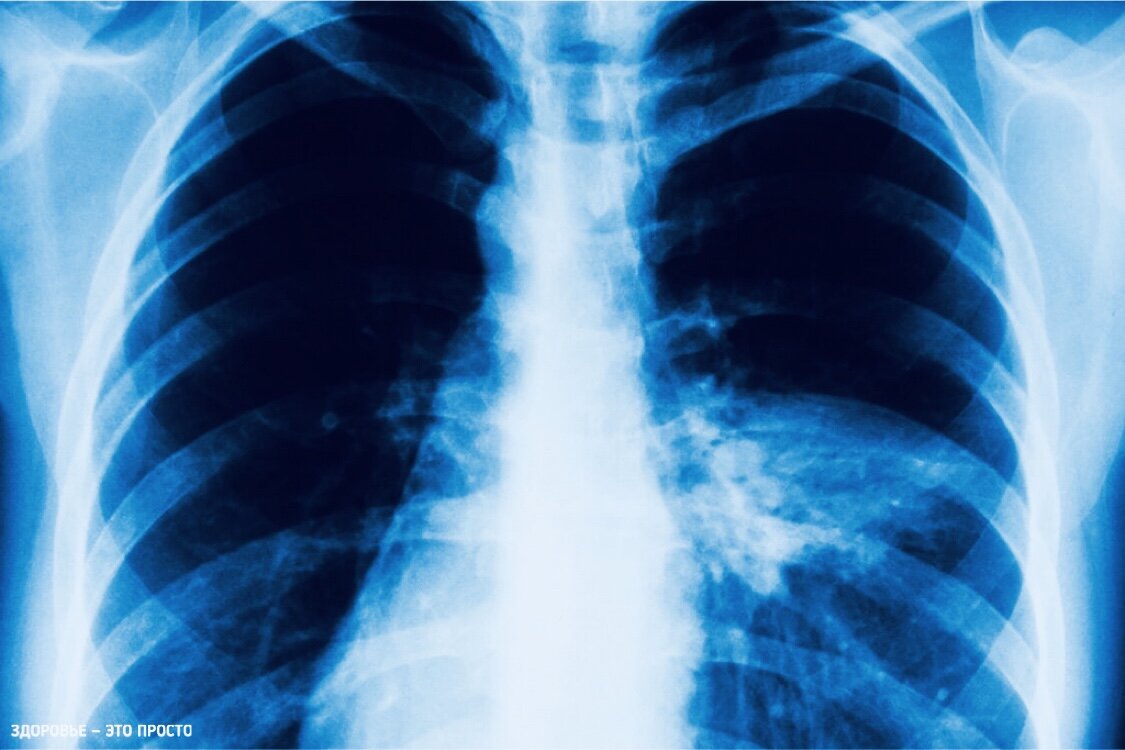

Примерно так можно проиллюстрировать пневмонию